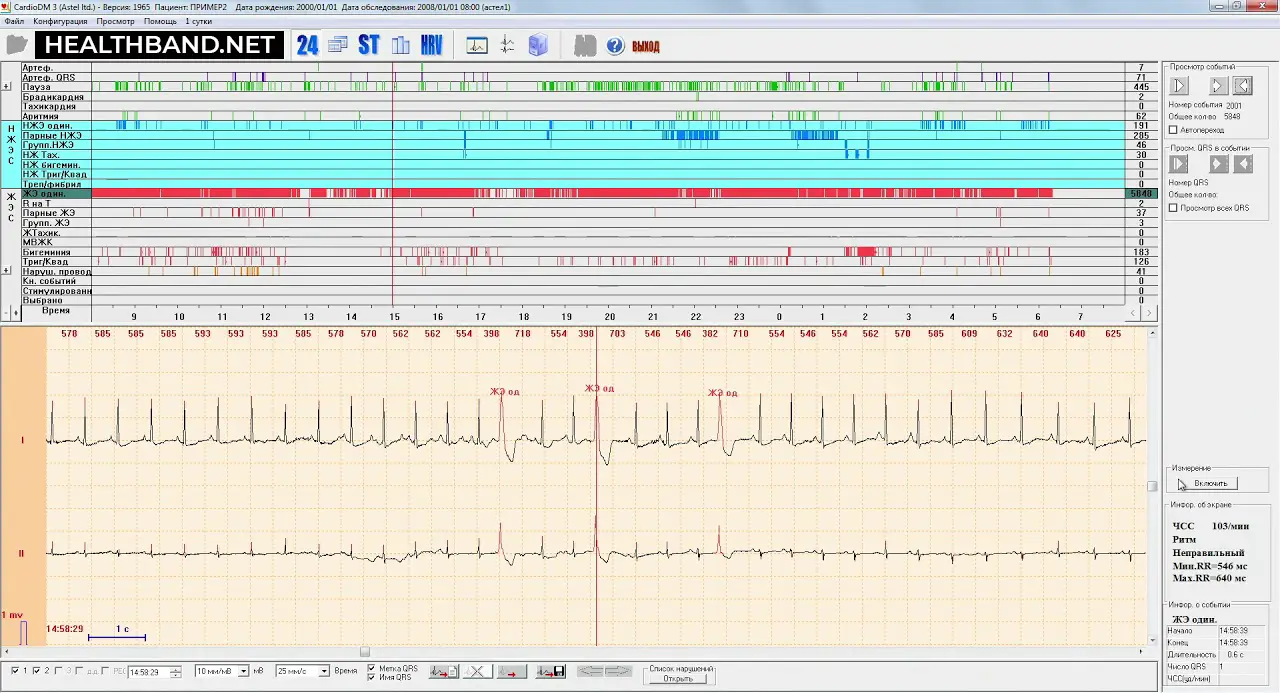

Запись с прибора загружают в специальную программу. Она анализирует показатели работы сердца и автоматически подсчитывает:

- количество наджелудочковых и желудочковых экстрасистол;

- длительность и частоту приступов тахикардии;

- минимальную, среднюю и максимальную ЧСС за сутки;

- паузы в работе сердца и эпизоды нарушения проводимости;

- вариабельность сердечного ритма.

Также программа анализирует динамику сегмента ST и другие признаки ишемии. Результаты холтера просматривает специалист и, если видит типичные изменения, сопоставляет их с временем активности, симптомами, приёмом лекарств и другими событиями. Далее он выносит заключение и решает, нужны ли дополнительные исследования.